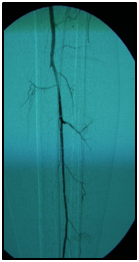

Endovascular procedure was done with antegrade access in the ipsilateral common femoral artery, diagnostic angiography confirmed: Patency of the femoral-popliteal axis, occlusion of the posterior and anterior tibial arteries, two critical stenotic lesions in the fibular artery and revascularization of the dorsalis pedis and plantar arteries by the fibular artery. To treat the fibular critical atherosclerotic lesions were performed a percutaneous transluminal angioplasty using a 0.0018in.guidewire, catheter support and a catheter balloon (3,0x6 mm and 3,5x 15mm).

Final angiographic control showed patency of the fibular artery and dorsalis pedis, with direct flow for the first metatarsal artery, thus guaranteeing enough flow to heal the ulcer in six months after the procedure. In conclusion endovascular treatment has a high technical eligibility with good reported outcomes and represents an alternative for diabetics with CLI Disease (Figure 1 and 2).

• Figure 2 From left to right showing percutaneous transluminal BTK balloon angioplasty, and revascularization of the dorsalis pedis and plantar arteries by the fibular artery.